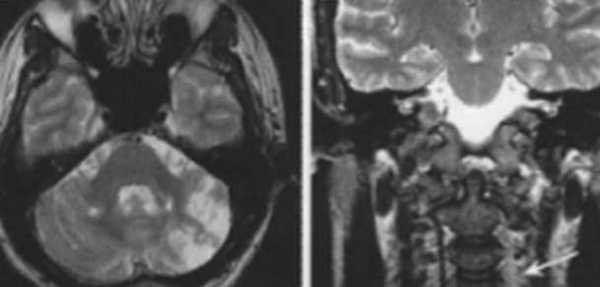

Внутримозговая гематома (граница острой и ранней подострой стадий - 3 суток), осложнившаяся внутрижелудочковым кровоизлиянием.

Внутримозговая гематома, поздний подострый период (14-21 день) с перифокальным отеком вокруг гематомы.

Внутримозговая гематома правой теменной доли. Граница поздней подострой и ранней хронической стадии. В Т2-ВИ виден ободок гемосидерина (стрелка).

Хочется подчеркнуть возможность МРТ в выявлении последствий геморрагического поражения - остается хорошо дифференцируемый по Т2 ободок гемосидерина, недоступный для визуализации при других методах нейровизуализации.

Стрелками показан ободок гемосидерина по периферии постишемической кисты.